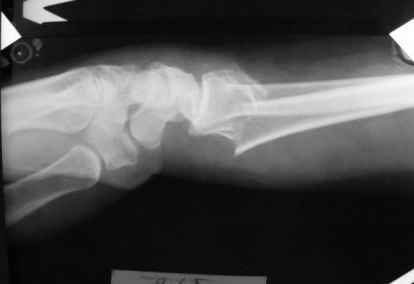

Уважаемые коллеги.Прошу обсудить случай лечения перелома дистального метаэпифиза лучевой кости. Ситуация скандальная и крайне неблагоприятная. Больная с патологической обстоятельностью мышления, склонностью к сутяжничеству, патологическими умозаключениями, не поддающимися коррекции (см. психиатрию, правда офиц. диагноза нет). В данном случае есть ряд ошибок с нашей стороны, прежде всего в отношении качества ведения документации (за что получил административное взыскание, по делом мне дураку). В остальном- придерживались в лечении подхода классический советской школы. Так как умную операцию…… сами знаете… 15.12- перелом луча в Москве. Там же репозиция, гипс. Дальнейшее лечение у нас в ЦРБ. 20.12.- вторичное смещение в гипсе21.12- под внутривенным наркозом- репозиция, гипсовая лонгета. Дальше начинается самое интересное. После репозиции больная заявила, что я (репозицию делал я) порвал ей все связки в суставе, посинел у нее 5 палец, якобы я за него тянул и т. д. На самом деле на 2 сутки после репозиции рука немного отекла и было незначительное сдавление гипсом, который был ослаблен. Дальнейшее лечение консервативное. Через 6 недель- гипс снят, назначено ЛФК. Пациентка крайне недовольна. Говорит, что на снимке у нее выступает кость, я ей сломал руку и.т.д. В общем началось. Пациентка прочитала в интернете наверное все, что есть по данной травме.По заключениями рентгенологов и консультанта из КДЦ областной больницы - стояние отломков допустимое. Объективно говоря- снижена высота лучевой кости, диастаз лучелоктевого сочленения, и не сросся шиловидный отросток. однако на РКТ при сравнении с другой стороной- разница незначительная. Дальше в одной из больниц нашей области и одной из больниц Москвы (вроде бы КГБ 53) врачи сказали, что репозиция сделана плохо. Нужна операция (восстановить длину лучевой кости), даже один из них предложил РЕДРЕССАЦИЮ (хи-хи) с наложением аппарата Илизарова. Что это для данной больной- радость неописанная. (см. описание психического статуса). Ничем другим, кроме зарабатывания дешевого авторитета объяснить данный факт не могу.Кстати, у больной еще нейропатия локтевого нерва.Для разрешения конфликта больная направлена на консультацию в ЦИТО на 03.03.11.

1. РЕПОЗИЦИЯ сделана качественно(ОСНОВНЫЕ 2 УГЛА ВЫСТАВЛЕНЫ ПРАВИЛЬНО ) , но перелом нестабильный и склонен к втор смещению . Поэтому мы стараемся все переломы со смещением фиксировать 3-МЯ спицами по GRIN методике .

2. По сравнению и без ! втор смещение незначительное.НЕТ НИКАКОЙ ,,локтевой косорукости,,маделунгов . но имеется смещение совести у врачей КГБ 35--НЕТ ЗДОРОВЫХ, есть только недообследованные ! Этому смещению аппарат внешней фиксации не поможет .Психопаткам в менопаузе да весной только этого и надо чуть толкнули и поехало .

1. Репозиция от 21.12.10 была выполнена лучше, чем первичная.

2. Укорочение лучевой кости с изменениями дистального лучелоктевого сустава требует оперативного лечения

Заключение: Консолидированный в неправильном положении перелом дистального метафиза левой лучевой кости. Ротационная контрактура левого предплечья. Рекомендовано- разработка, консультация через 2 месяца.

2.Укорочение лучевой кости и лучелоктевой диастаз невелики,но отрицать их клиническую значимость весьма сложно.

3.Исходя из конкретной ситуации и здравого смысла абсолютных показаний к операции не было и сразу после травмы и нет сейчас ,уже после сращения,поскольку перелом внесуставной,а осколок по тылу луча не препятствует торцевому упору по волярному краю луча.